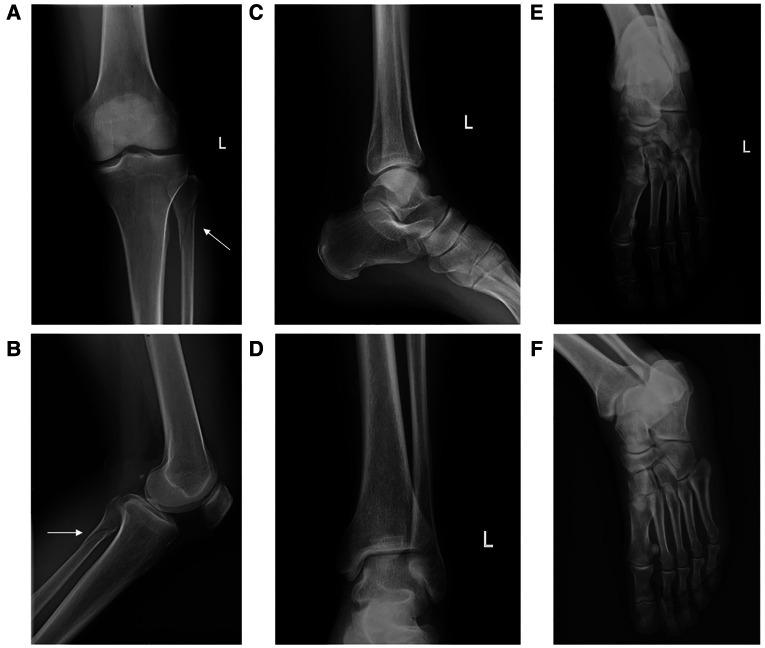

Nonoperative treatment of avulsion fracture of the anterior tibia with proximal fibular fracture: A case report.

A 48-year-old male reported pain in the lateral part of his left lower leg and ankle during a badminton play. Physical examination revealed tenderness and swelling of the lateral aspects of the left ankle, as well as the proximal aspect of the fibula. Preoperative plain x-ray image, computed tomography, and magnetic resonance imaging revealed an avulsion fracture of the anterior tibia by the anterior inferior tibiofibular ligament without medial and posterior fracture, rupture of the deltoid ligament, or interosseous membrane. Nonoperative management was performed and successful recovery was observed at a 6-month follow-up.

Nonoperative management can be a better option for some variations of Maisonneuve fracture with a stable ankle joint. The selection of treatment options should be based on careful examination and radiological evaluation of the ankle.